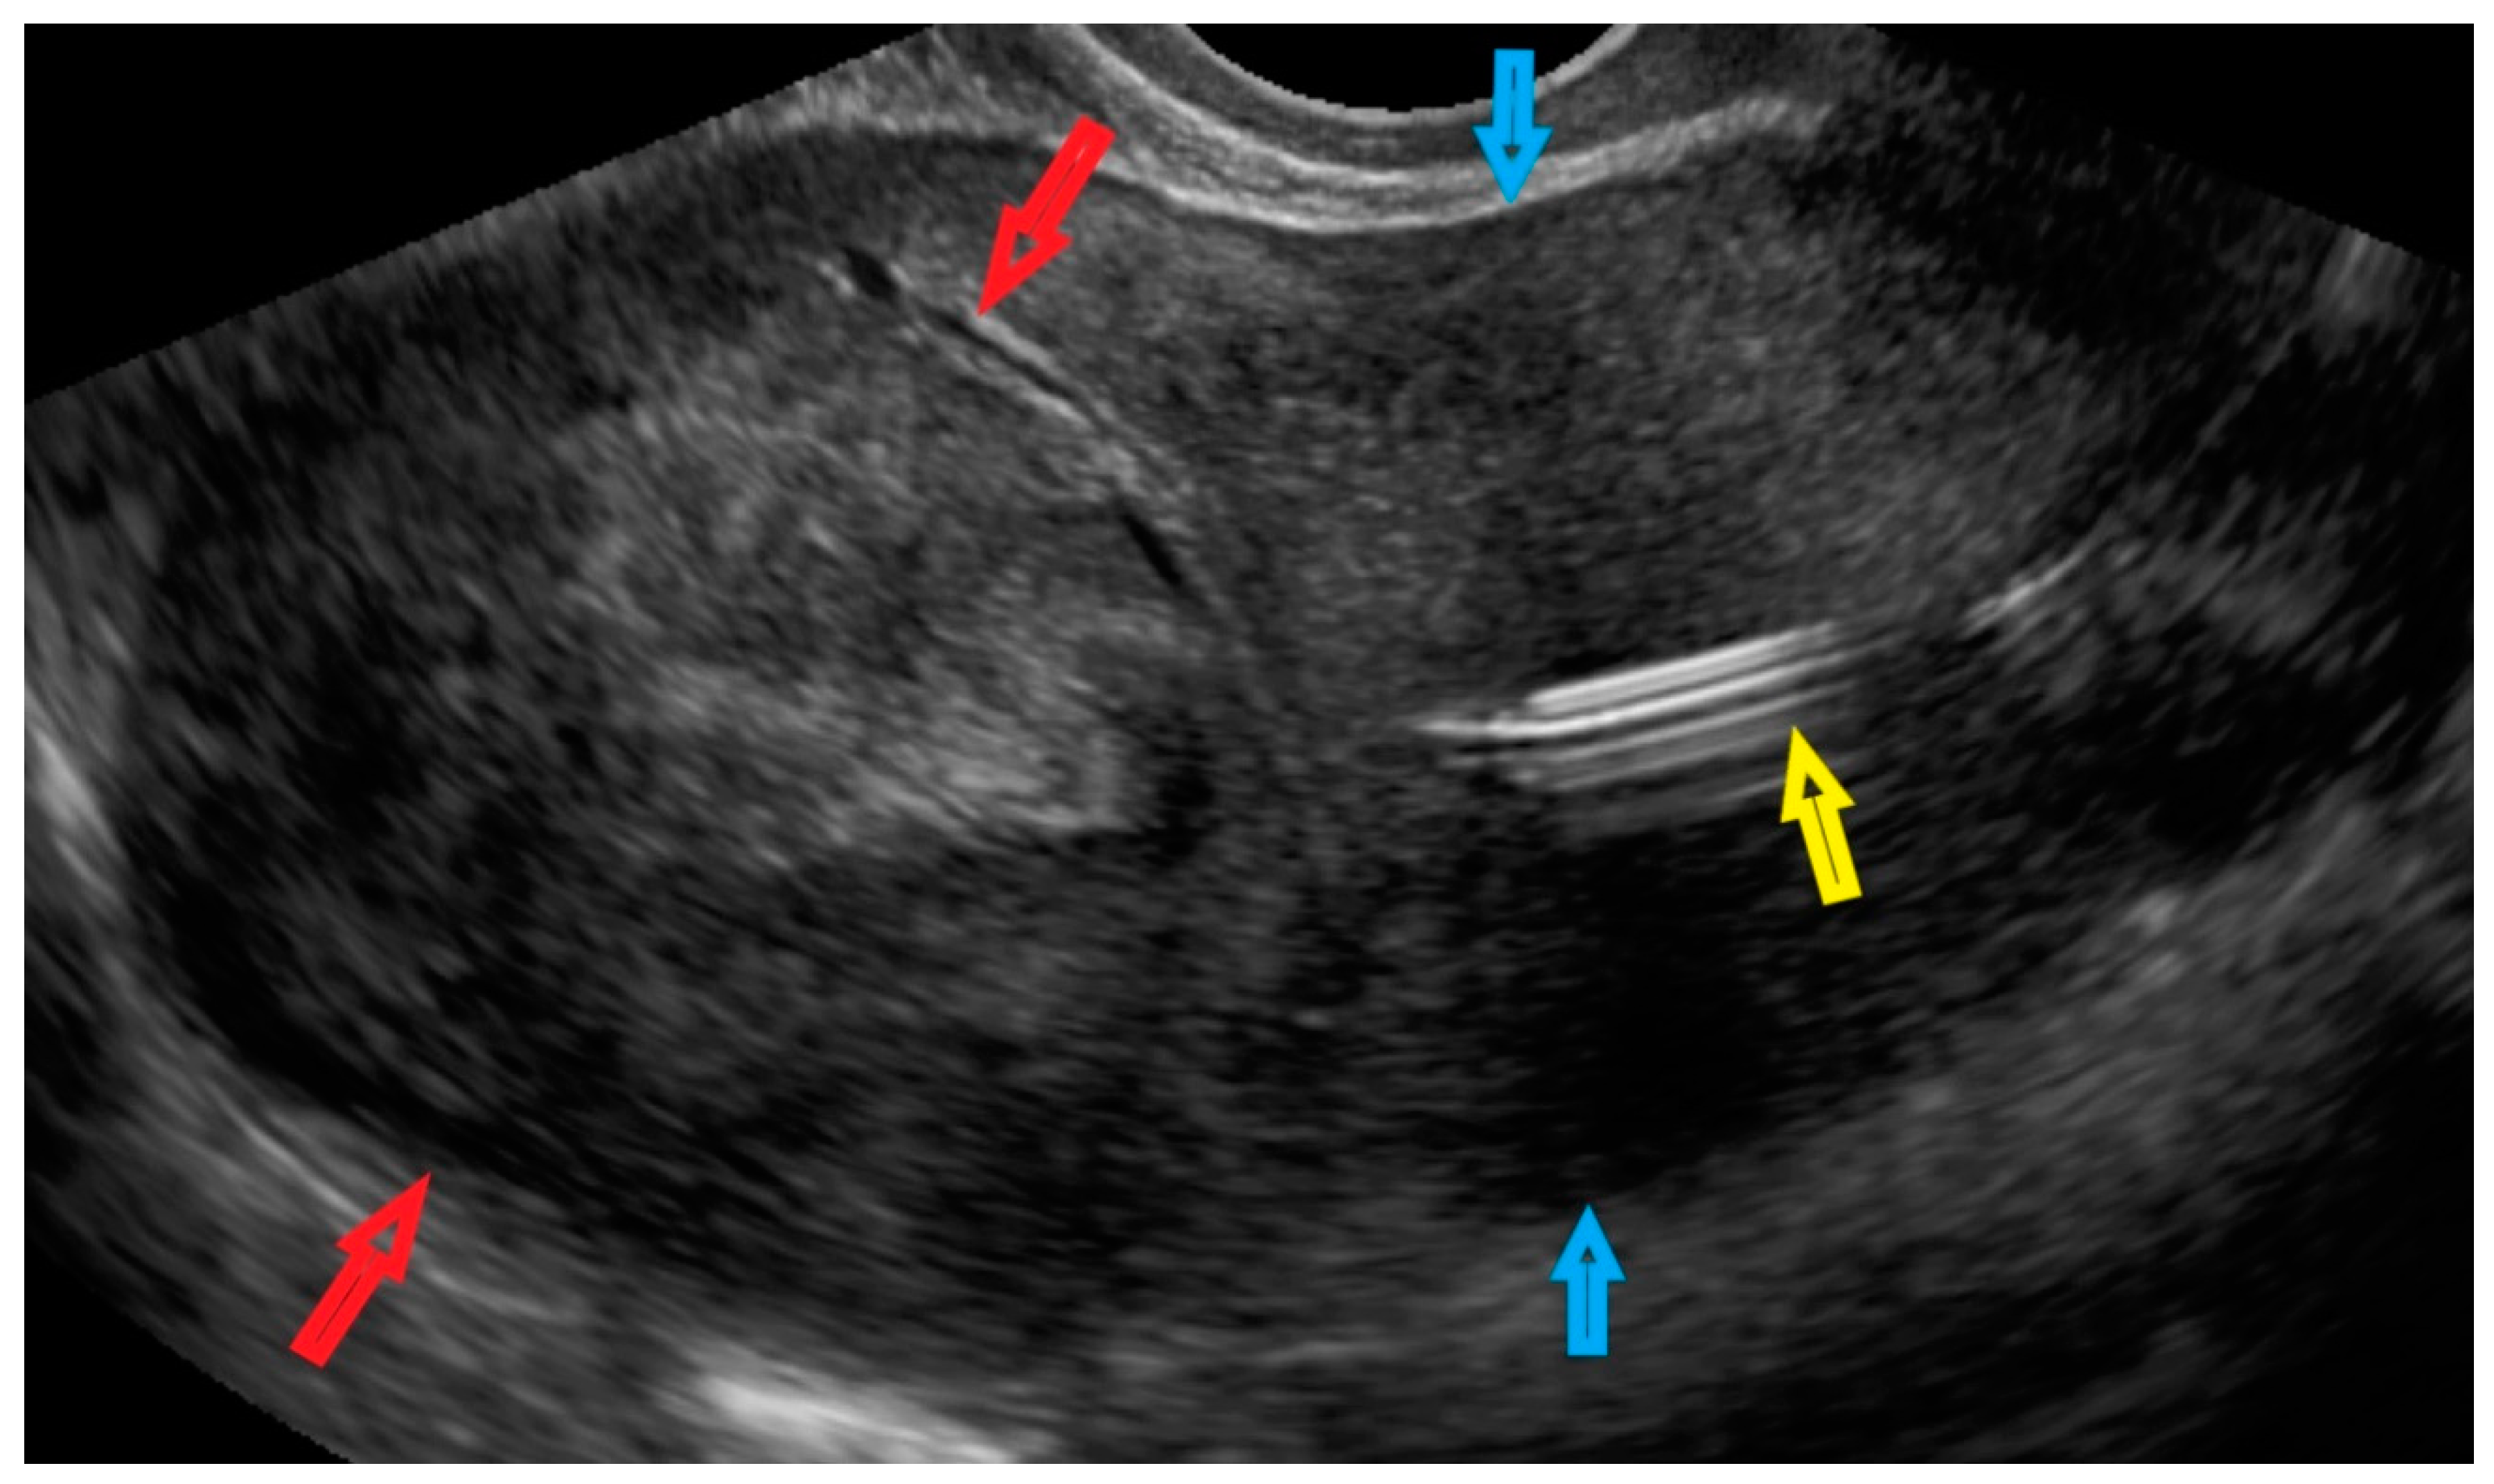

| 1 (44) | Typical uterine lesion (myoma) | Figure A1 | No | Yes | Leiomyoma, cellular variant (UG-TUC core needle biopsy) | Yes (lesion enlarged during follow-up) | Leiomyoma, cellular variant | No | Yes |

| 2 (36) | Sarcoma suspicion | Figure A2 | Yes | Tumorectomy, uterus preservation (young age) | LMS (UG-TUC core needle biopsy) | Yes | LMS | No | Yes |

| 3 (37) | Atypical uterine lesion | Figure A3 | Yes | No | Lipoleiomyoma (UG-TUC core needle biopsy) | No | - | Yes | Yes |

| 4 (56) | Atypical uterine lesion | Figure A4 | Yes | Yes | Leiomyoma (transvaginal ultrasound guided core needle biopsy) | Yes | Leiomyoma and adenomyosis | Yes | No |

| 5 (50) | Atypical uterine lesion (metastatic adenocarcinoma G3 in inguinal lymph node) | Figure A5 | Yes | No | Leiomyoma (UG-TUC core needle biopsy) | No | Uterus / tumor not resected because primary urological carcinoma was diagnosed | Yes | Yes |

| 6 (38) | Atypical uterine lesion | Figure A6 | Yes | No | Leiomyoma, epithelioid variant (UG-TUC core needle biopsy) | Yes (lesion enlarged during follow-up) | Leiomyoma, epithelioid variant | Yes | Yes |

| 7 (29) | Atypical uterine lesion | Figure A7 | Yes | Yes | Leiomyoma (UG-TUC core needle biopsy) | Yes | Leiomyoma with signs of degenerations | Yes | Yes |

| 8 (52) | Atypical uterine lesion | Figure A8 | Yes | Yes | Total abdominal hysterectomy performed without core need biopsy, because of patients age and lesion ultrasound pattern recognition. Note: frozen section result: leiomyoma | Yes | STUMP | - | - |